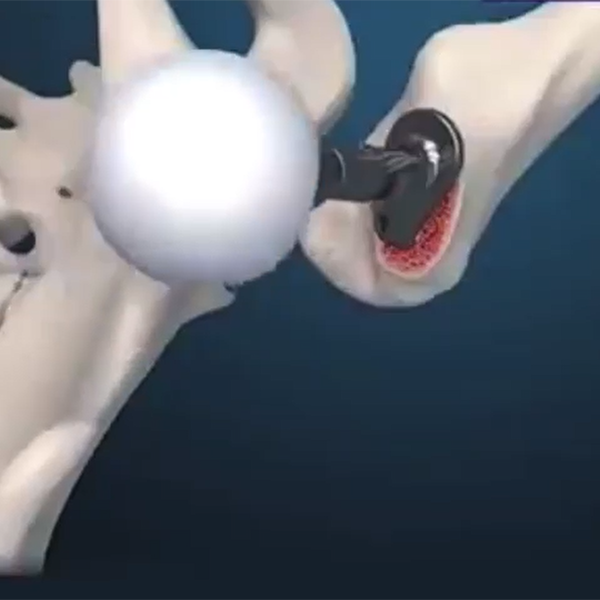

Artroplasti Kalça Protezi

- Kalça Anatomisi

- Kalça Kırıkları

- Osteosentez

- Protez Uygulamaları

- Kalça Protezi Tarihçesi

- Parsiyel Kalça Protezi

- Femoral Stem Çeşitleri

- Bipolar Kalça Protezi Uygulaması

- Total Kalça Artroplastisi

- Kalça Protezi Ameliyatları

- Uygulamalar

- Asetabular Kaplar

- Çimentolu ve Çimentosuz Femoral Stem